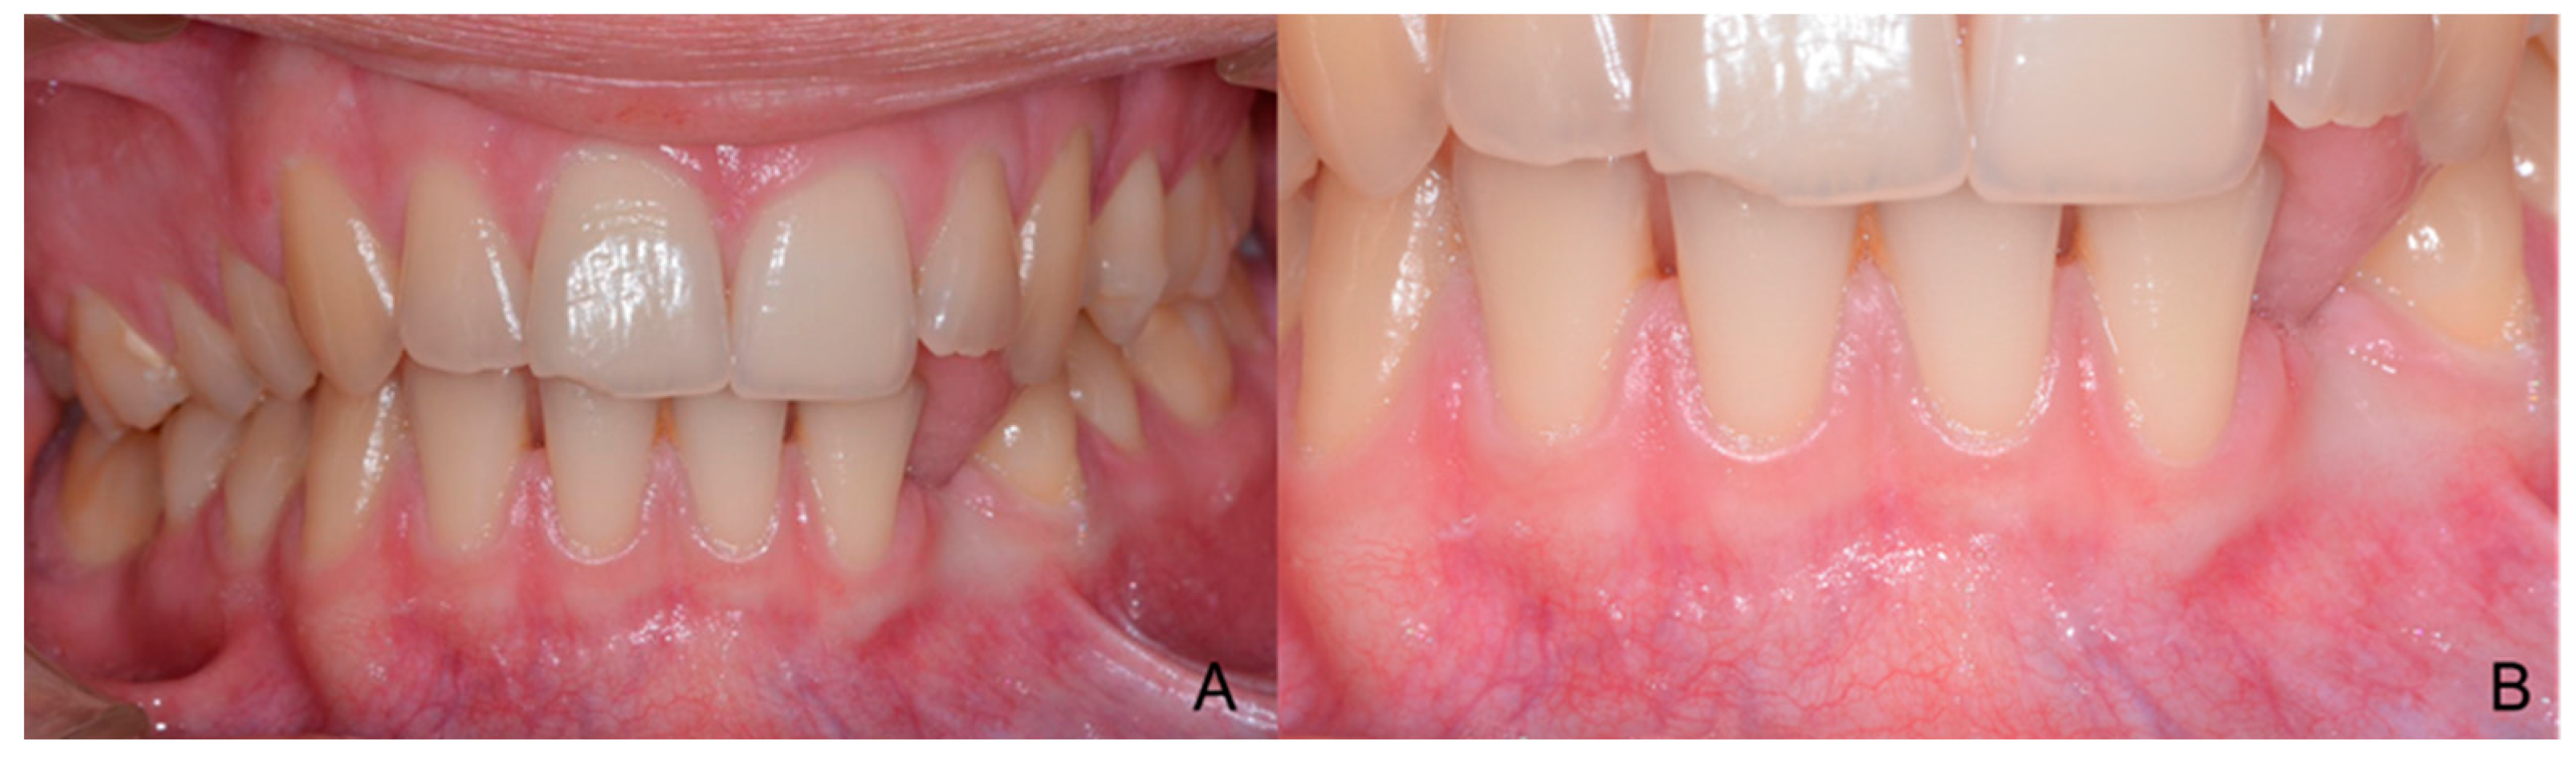

1.3. Case Number 3